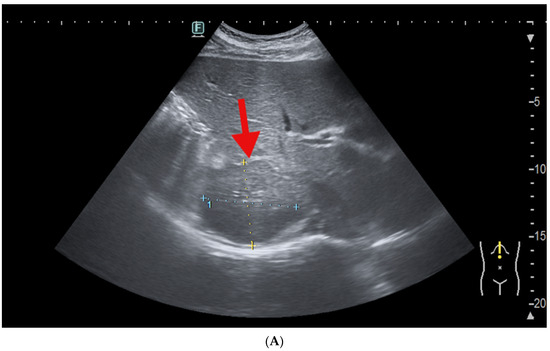

2.5. Imagery Scans